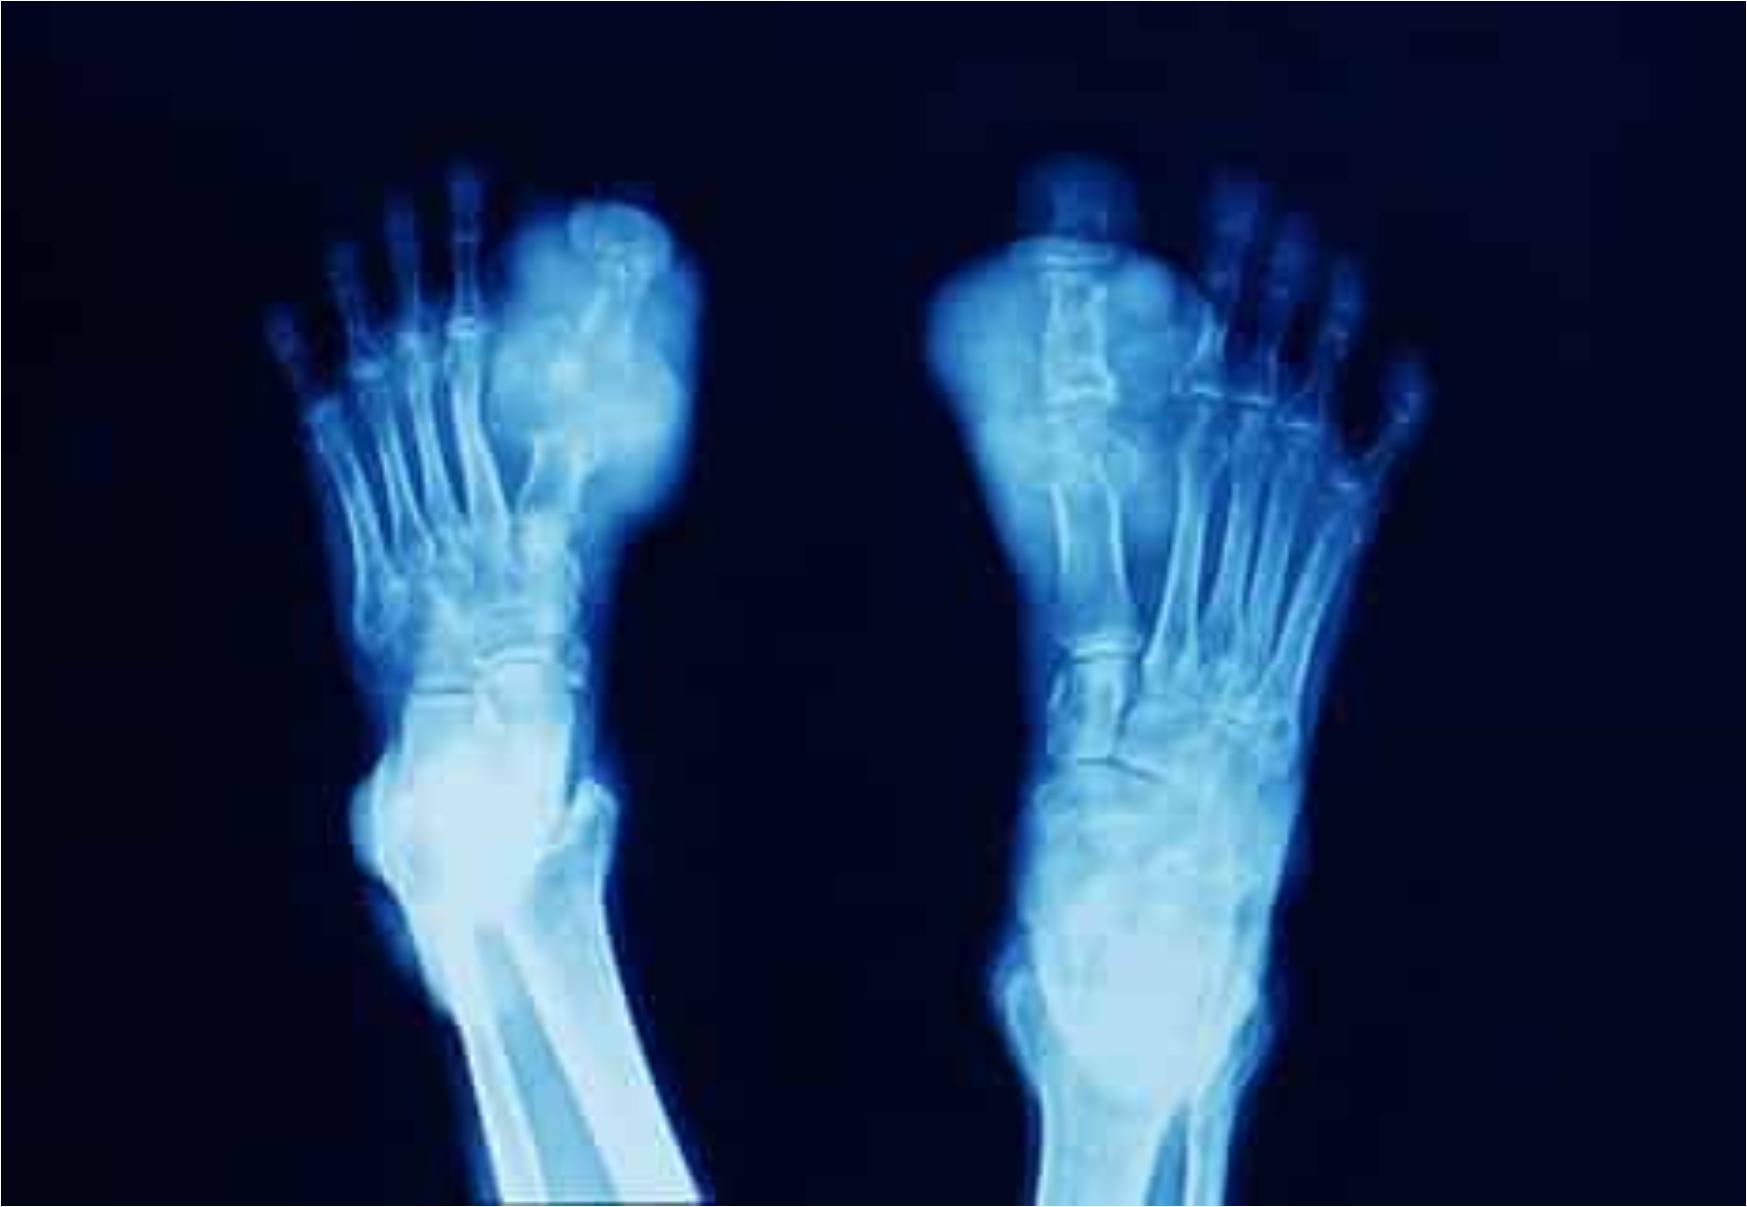

Η ουρική αρθρίτιδα είναι μια χρόνια φλεγμονώδης αρθροπάθεια. Είναι ενδεχομένως η συχνότερη φλεγμονώδης πάθηση των αρθρώσεων. Παλιά ήταν γνωστή και ως «ποδάγρα» λόγω της συχνής εντόπισής της στο μεγάλο δάχτυλο του ποδιού. Ο όρος, όμως δεν χρησιμοποιείται πλέον καθώς η άρθρωση αυτή (1η μεταταρσιοφαλαγγική) δεν είναι η μόνη που προσβάλλεται από τη νόσο.

Στα κάτω άκρα, εκτός από την πρώτη μεταταρσιοφαλαγγική άρθρωση (το μεγάλο δάκτυλο του ποδιού) στην οποία οφείλεται και η παλιότερη ονομασία της νόσου προσβάλλονται οι ταρσοί, οι ποδοκνημικές αρθρώσεις και τα γόνατα, ενώ στα άνω άκρα οι καρποί, οι αγκώνες και τα δάκτυλα των χεριών.

Η ουρική αρθρίτιδα, χωρίς την κατάλληλη φαρμακευτική αγωγή, οδηγεί σε μόνιμη παραμόρφωση και καταστροφή των πασχουσών αρθρώσεων. Εκτός από αυτές τις μόνιμες βλάβες στις αρθρώσεις όμως, τα αυξημένα επίπεδα ουρικού οξέος μπορεί να οδηγήσουν σε νεφρικά προβλήματα όπως η λιθίαση και η νεφρική ανεπάρκεια, σε καρδιαγγειακά προβλήματα όπως η αρτηριακή υπέρταση και να συνδυάζονται με υπερλιπιδαιμία (αυξημένη χοληστερόλη και τριγλυκερίδια). Συνήθως τα άτομα με ουρική αρθρίτιδα είναι παχύσαρκα και πάσχουν από το λεγόμενο μεταβολικό σύνδρομο.